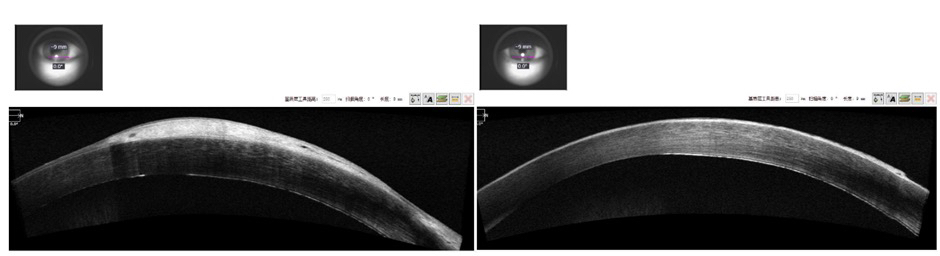

✦ OCT检查(术前VS术后)